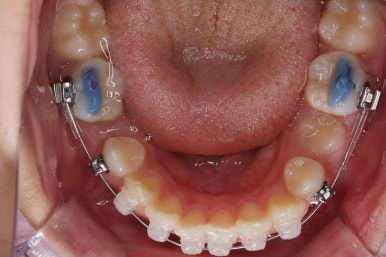

아래쪽이 더 시급하므로 브라켓 부착을 하여 가지런히 하기 시작했고 위쪽은 악궁확장장치를 입천장에 하여 위턱뼈를 가로로 넓혀주기 시작합니다.

악궁확장장치는 총 4-6개월 정도 부착하고 있으며 그 이후에는 입안에서 제거하게 됩니다.

윗니에도 이제 장치를 모두 붙였습니다. 아래쪽은 어느 정도 가지런해지고 나면 부족한 자리를 만들어주기 시작합니다.